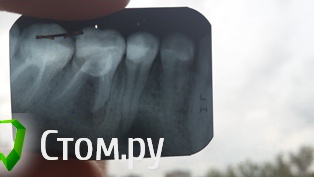

Natalia83 Опубликовано 13 августа, 2014 Поделиться Опубликовано 13 августа, 2014 Добрый вечер! Прилагаю снимок. Проблема с зубами 5 и 6 нижние. Скажите нужно удалять, делать резекцию (предлагает один врач) или можно перепломбировать каналы и костная ткань может восстановиться (так предлагает другой врач). Ничего не болит. Но месяца два назад была припухлость, было больно кусать. К врачу не было возможности пойти, несколько дней мазала "звездочкой". Все прошло и более 2х месяцев не беспокоит. Подскажите пожалуйста, что делать ?p.s. Черная черточка вверху - это скрепка на снимке. Ссылка на комментарий